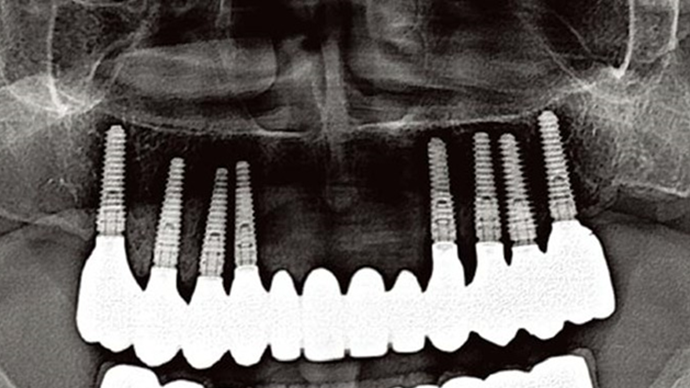

Clinical case: A Full transition from natural teeth to all-on-6 bridges

with AnyRidge implants

“AnyRidge shows excellent esthetic results

with Zirconia prosthesis in full-mouth rehabilitation case . ”